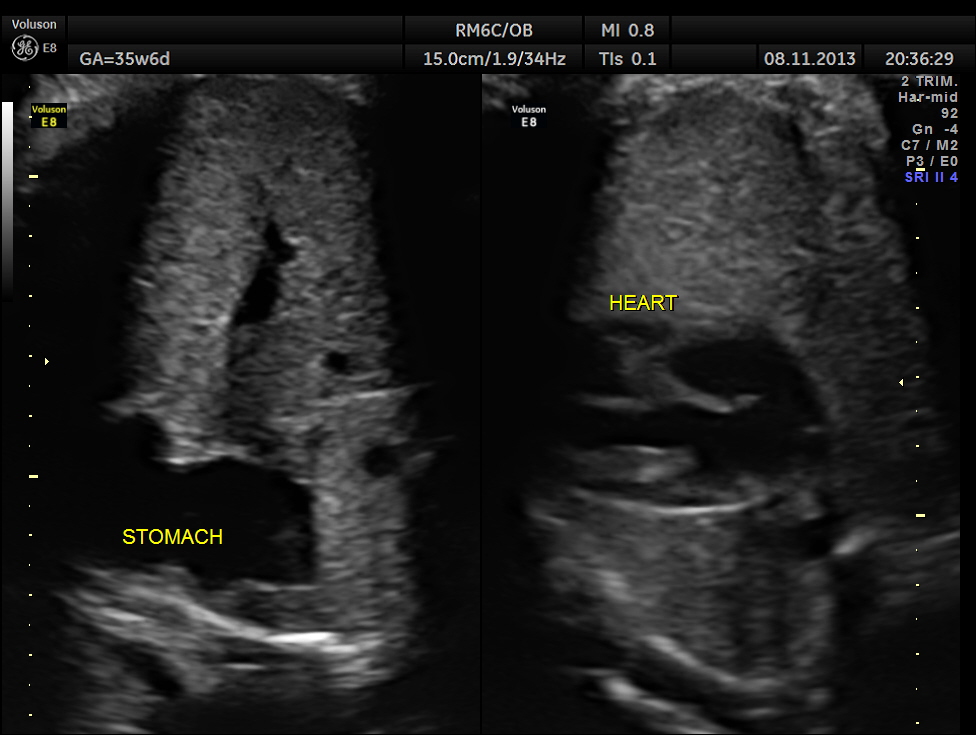

The scan was repeated at 36 weeks of gestation.

BPD, HC show < 2.3 % tile.

AC and FL appear to be normal.

the umbilical artery doppler appears normal.